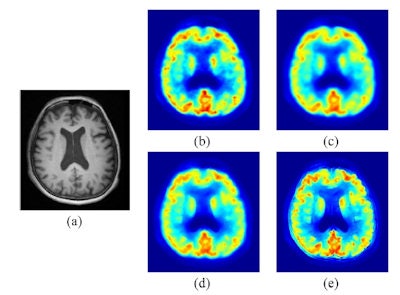

a) The MRI Zubal phantom with 5% Rician noise; (b) the true PET image at frame 11; (c) typical reconstructed image at frame 11 by FBP for one realization; (d) PET image filtered using Gaussian filtering; (e) PET image filtered by MRI-guided filtering; (f) PET image corrected by MRI-guided PVC."We aimed to develop fast voxel-wise filtering and partial volume correction techniques to improve the signal-to-noise ratio and spatial resolution of brain PET images with the help of high-definition structural MR images," said Jianhua Yan, from CIRC.

A typical PET image reconstructed by filtered back projection (FBP) was seen to be highly noisy. Gaussian filtering effectively smoothed the noise, but also blurred the edges within the image. Images produced by MRI-guided filtering and MRI-guided PVC exhibited dramatically reduced noise. In addition, MRI-guided PVC further improved the resolution recovery, as seen in thin structures such as the occipital cortex.

A profile through the PET image was used to quantitatively compare PET intensity recovery from the images. As expected, loss of edge structures was most obvious in the Gaussian filtered image. Overall, MRI-guided filtering and PVC exhibited optimal performance, with MRI-guided PVC best at recovering intensity and resolving edge structures.

(a) T1-weighted MPRAGE MRI; PET images: (b) uncorrected; (c) Gaussian filtered; (d) MRI-guided filtered; (e) MRI-guided PVC.Four representative axial PET images (reconstructed without smoothing; Gaussian filtered; MRI-guided filtered; and MRI-guided PVC) showed that, again, MRI-guided PVC provided the best structure delineation while keeping noise under control. Profiles taken through the image also supported the finding that MRI-guided PVC can effectively recover intensity and improve contrast.